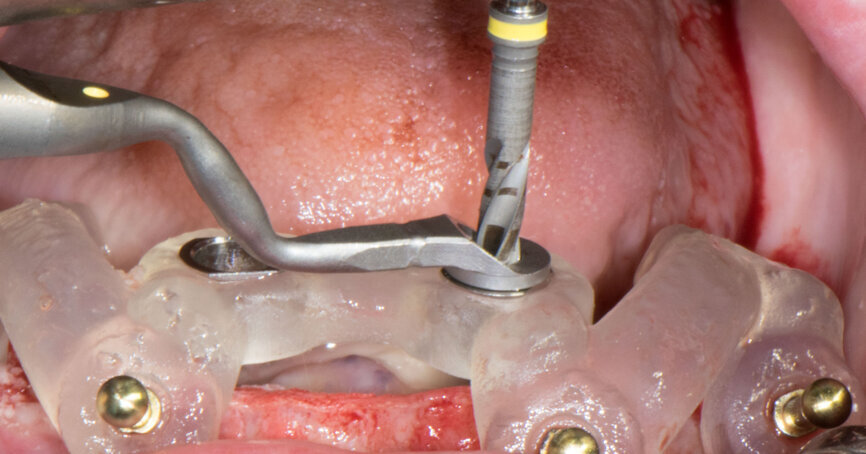

On the day of surgery, two impressions were taken: first with the guide for the pins for stable drilling (Fig. 9), then with the existing prosthesis (Fig. 10) for its correct conversion into an immediate restoration. The first mucosa-supported guide was used for drilling the sites for template fixation pins (Fig. 11). Next, the guide was removed, the flap was raised and the second guide was fixed with the pins at the corresponding sites (Fig. 12).

Implant beds were prepared (Figs. 13 & 14) and Straumann BLT implants placed with a torque setting of more than 35 Ncm, following the protocol to allow correct subsequent screw retained abutment placement (Figs. 15 & 16). Bone around the implants was prepared with bone profilers (Straumann) for the same reason (Fig. 17). The crest was flattened (Figs. 18 & 19), screw-retained abutments were screwed to 35 Ncm (Fig. 20) and covered with healing caps, and the wound was sutured (Fig. 21).